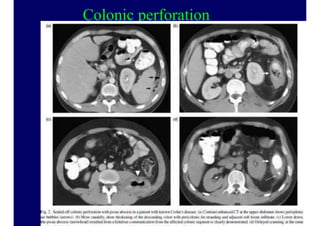

Colonic perforation

50